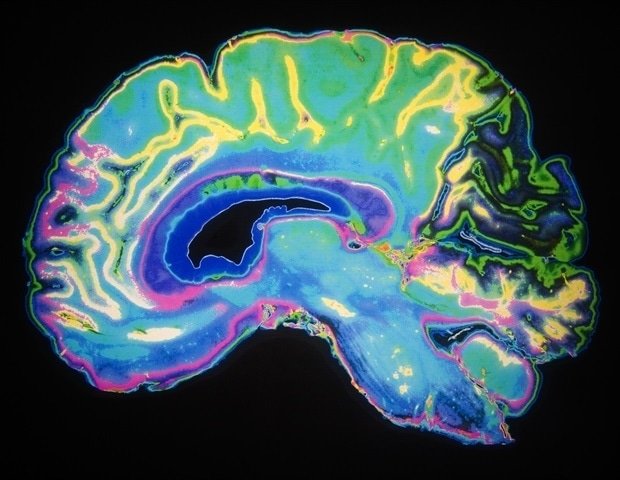

Mayo Clinic researchers have developed an experimental nanotherapy that delivers two anti-cancer drugs directly to brain tumors, according to a study published today. communication medicine. This strategy extended survival in preclinical models of glioblastoma, the most aggressive of brain tumors.

Glioblastoma is notoriously difficult to treat. Even with modern treatments such as surgery, radiation, and chemotherapy, patients typically survive about 15 months after diagnosis. One major challenge is that many drugs cannot effectively reach tumors in the brain, and those that do often lose effectiveness as tumors develop resistance.